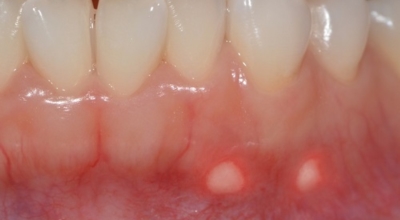

입안 점막이 동그랗게 패여 통증을 유발한다면, 아프타성 구내염을 의심할 수 있어요. 음식을 먹을 때마다 아픈 작은 궤양이 생겼다면, 아프타성 구내염을 의심할 수 있어요. 아프타성 구내염은 빨간색 둘레를 가진 둥근 형태의 흰색 궤양이, 얕은 깊이로 한 개 및 여러 개 생기며 통증을 동반하는 것이 특징입니다. 전 인구의 20~40%가 발병할만큼 통상적으로 나타나는 질환으로 20대, 주로 여성분들에게 많이 나타나며, 일주일 정도면 자연적으로 치유되지만 1~3개월 간격으로 빈번히 재발하는 것이 특징입니다.

까닭은 입 속 점막의 작은 상처나, 바이러스, 세균의 감염, 각별히 수면 부족이나 과로, 스트레스가 축적돼 면역력이 떨어졌을 때와, 비타민 B12 또는 엽산 결핍 시에 많이 생기 다고 알려져 있어요. 흔한 질환이니만큼 자연적으로 치유 되지만, 통증을 동반하고, 궤양의 크기가 커지거나 숫자가 늘어나기도 하기 때문에 연고나 외용제, 가글액 등을 활용해서 증상을 경감시키는 치료를 하기도 해요.